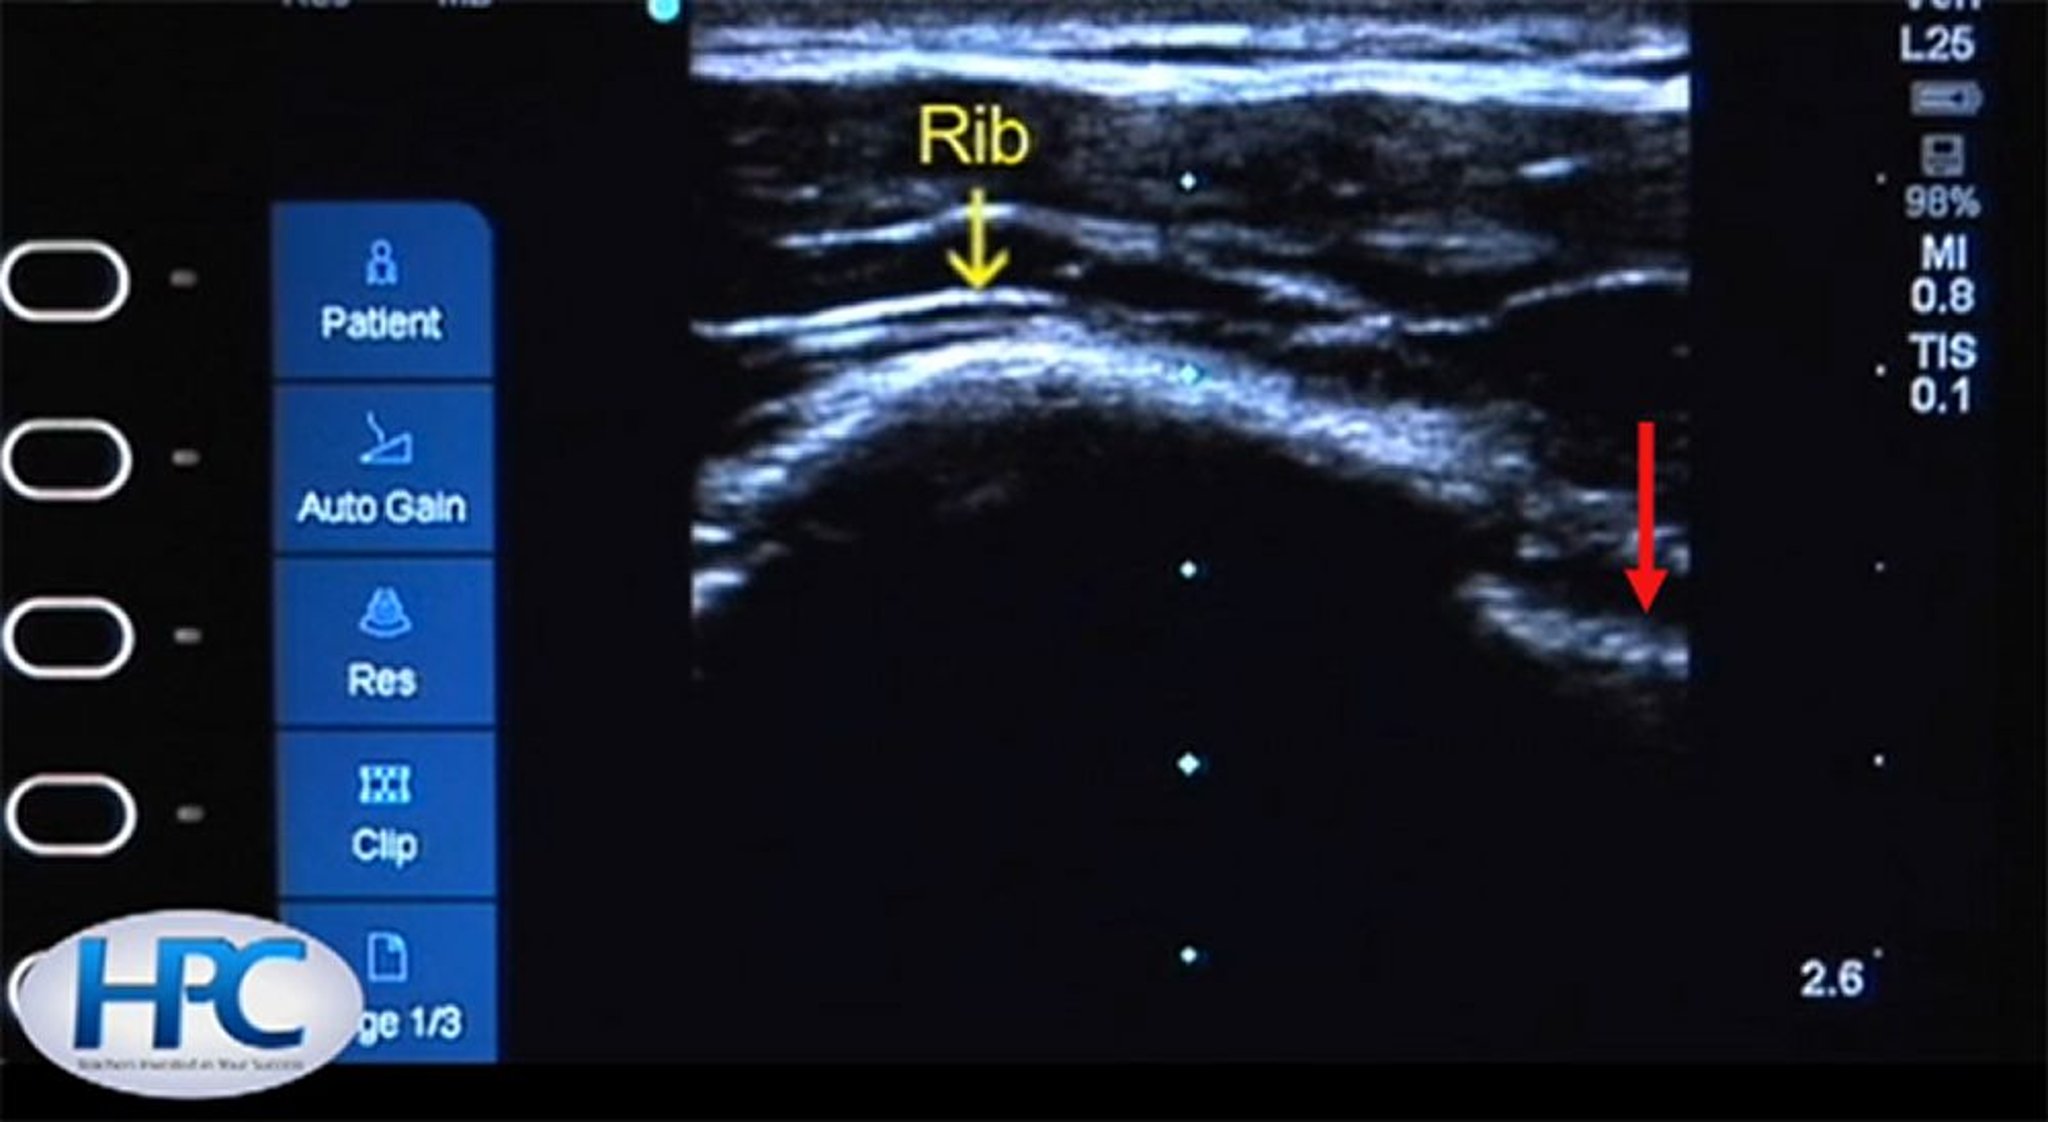

肋骨および胸膜線の超音波像

肋骨(黄色矢印)は高エコー(白色)の構造としてみられ,肋骨の下には陰がみられる。肋間に胸膜線(赤矢印)がみられる。